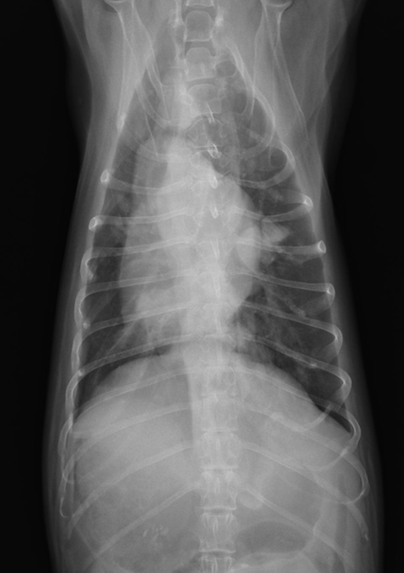

犬の肺原発血管肉腫。

わんちゃんに発生する悪性腫瘍の中でも進行が早くたちの悪い血管肉腫。このわんちゃんは咳や元気食欲の低下で偶然発見されました。

非常に怖い病気です。